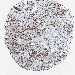

CANCER BREAST CANCER Show tissue menu

BRCA TCGA BRCA VALIDATION PROTEIN EXPRESSION

ANTIBODIES

AND

VALIDATION